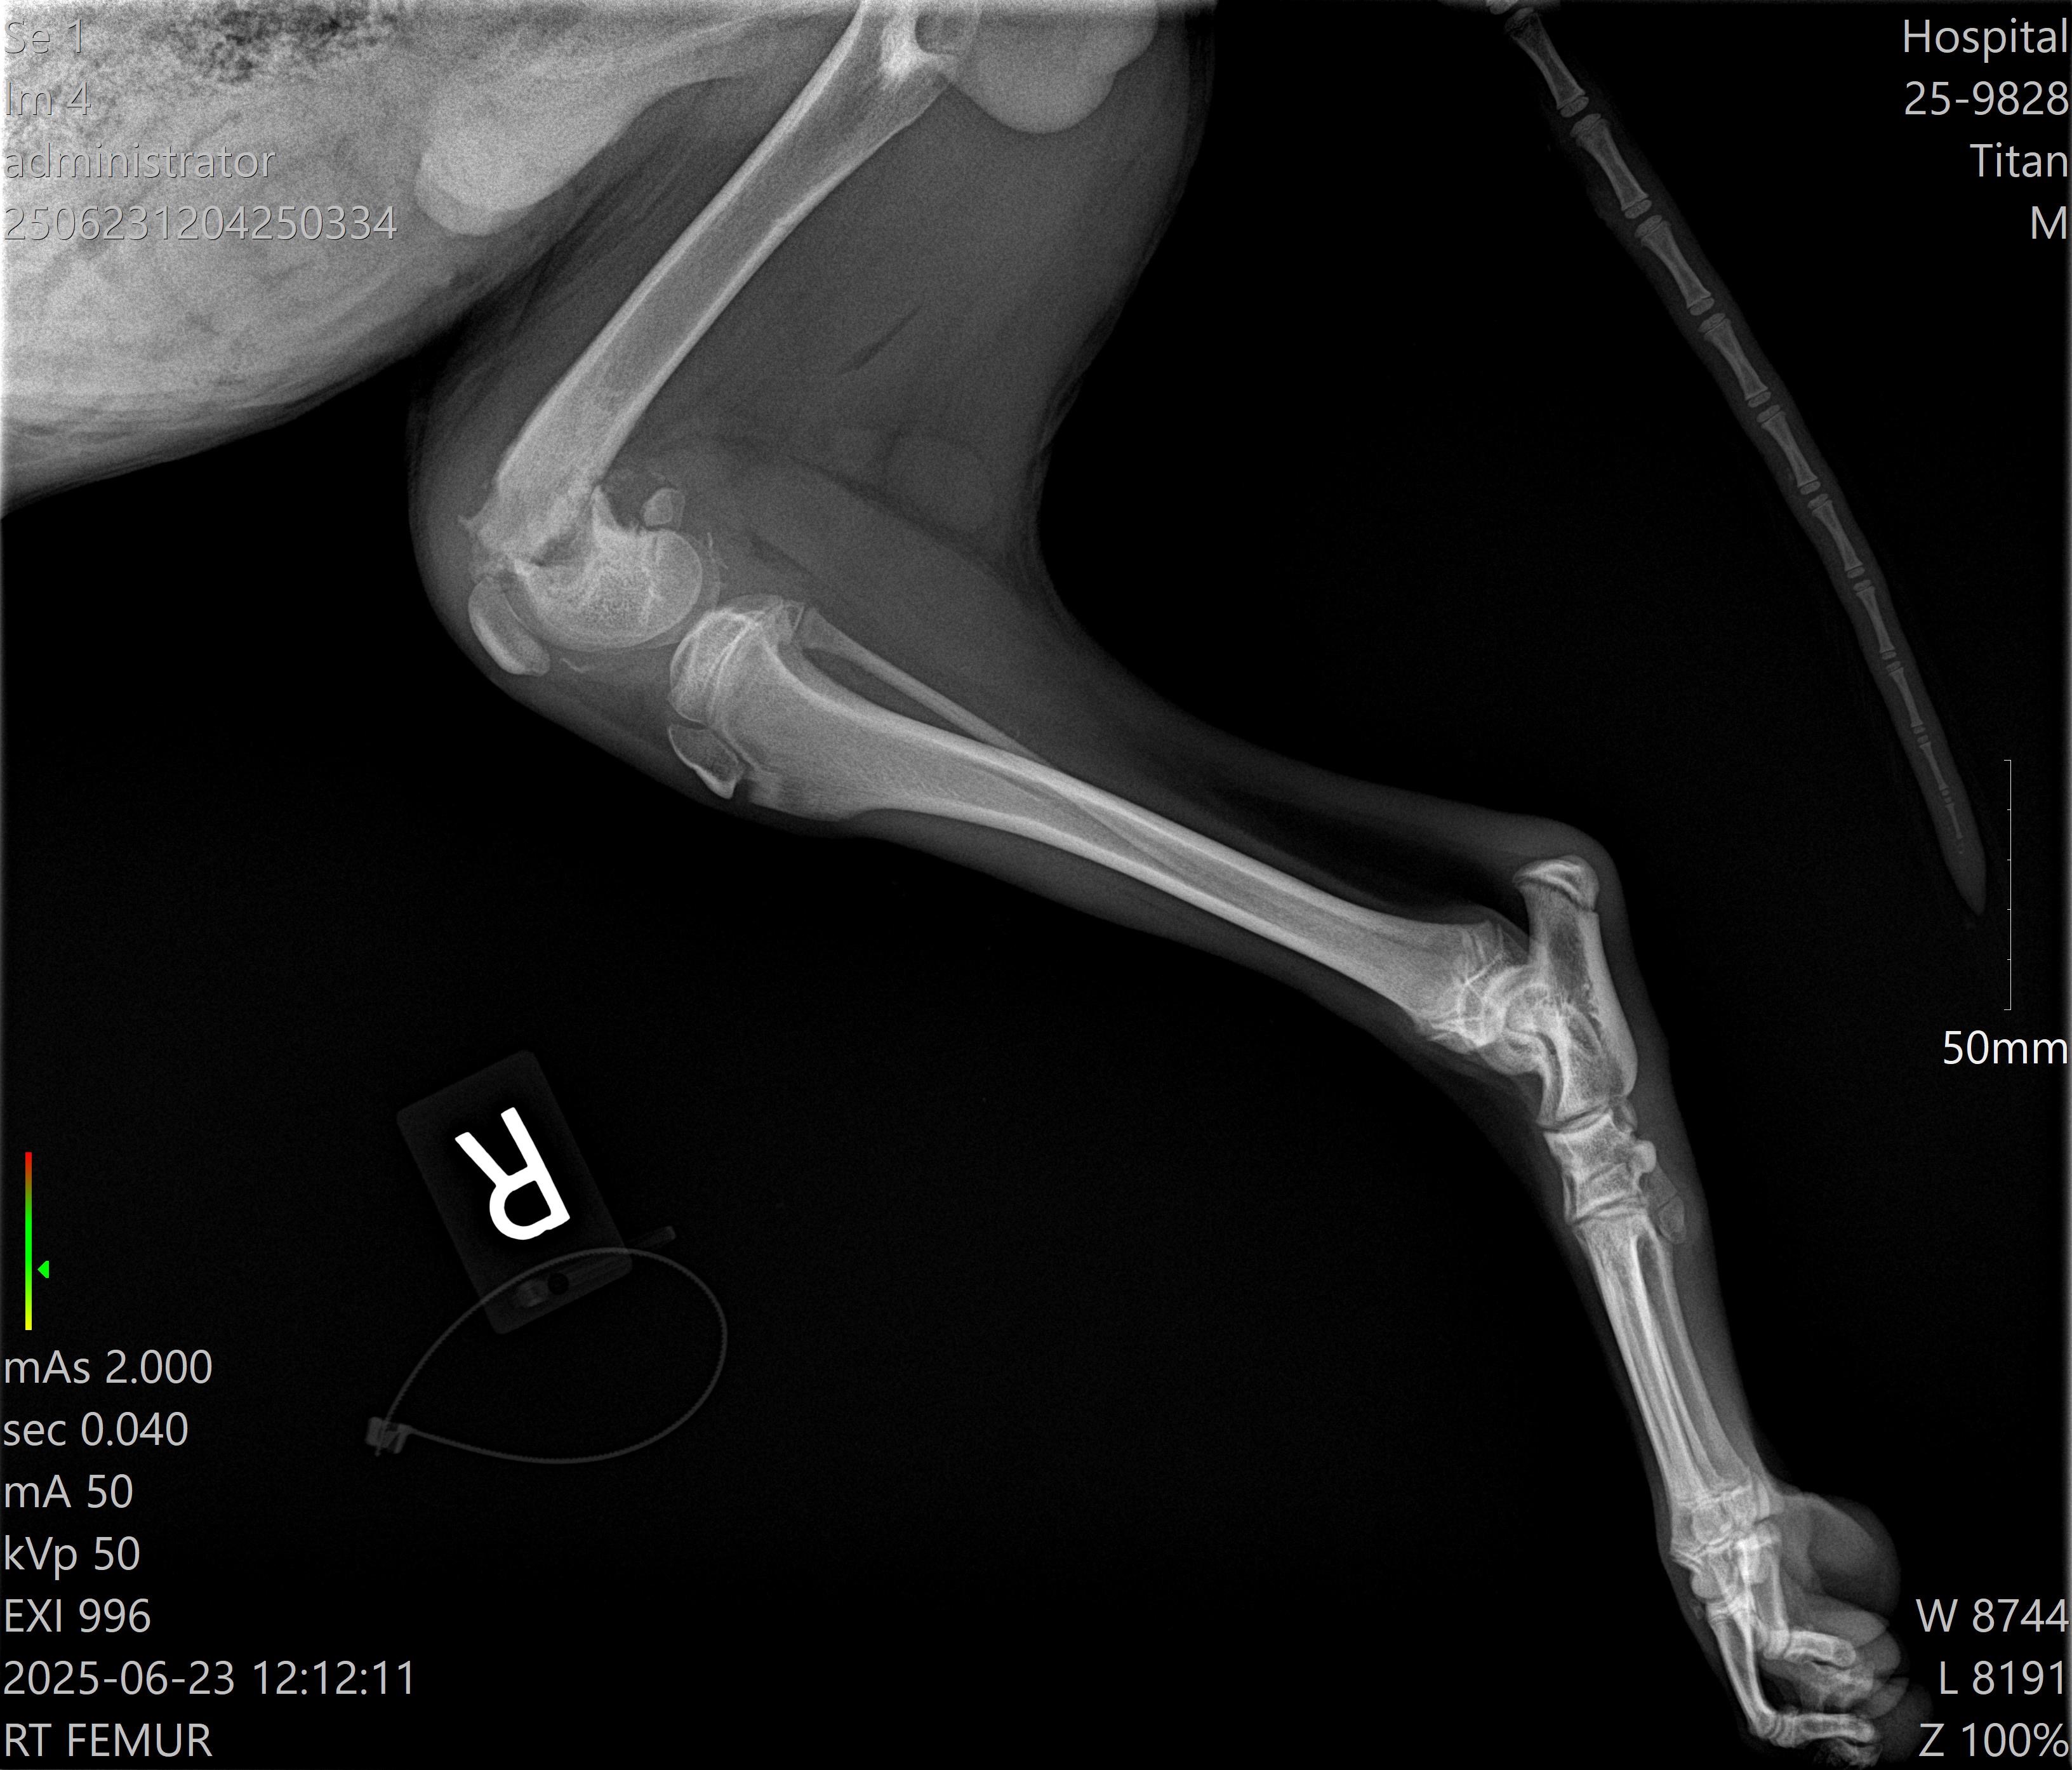

Hello, my name is Makayley! My boyfriend, Mark, and I live in Houston, Texas, and have recently found a very injured puppy. We found him barely able to walk on his back legs, really only using his front two legs to walk. We believe he has been hit by a car. We named him Titan, as we cleaned, fed, and loved him until we were able to take Titan to the vet this morning. The x-rays showed Titan has very bad fractures under both of his back knees. They have been trying to heal themselves, but they are not healing properly. The prognosis for Titan to heal on his own and/or with medication is very low and painful. The vet recommends surgery for each fracture. We do not want to put him down as he is so loving and wants to play with our other three dogs.

We have talked to a surgeon and he has seen both X-rays of Titans legs. He thinks we need to plate both of them. Meaning surgery on both of Titans legs. Please keep sharing and donating! We are so grateful for all of your help